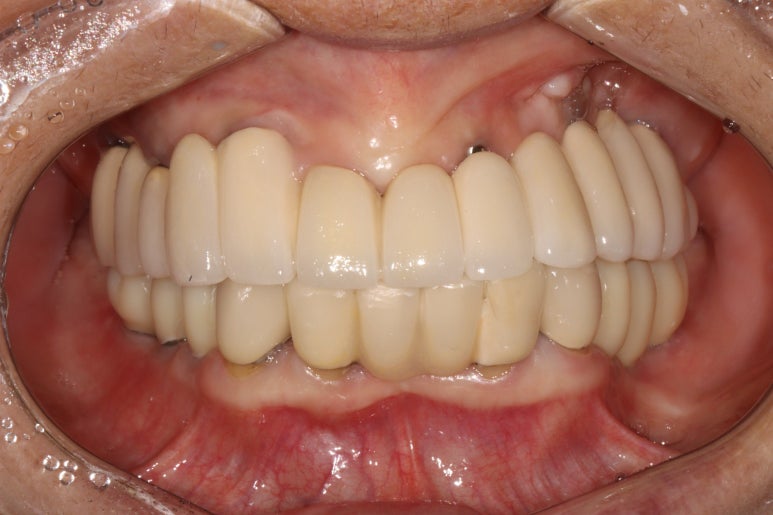

생각보다 임시치아보다 훨씬 매끈한 표면과 비슷한 색깔을 자랑하는 지르코니아 크라운입니다.

아마 어금니에 임플란트가 생긴건가? 싶으실거에요.

오스템 원가이드 네비게이션 임플란트 시스템을 이용하면, 정교하게 이상적인 위치에 임플란트를 심어낼 수 있어 자연스러운 임플란트 보철물을 제작하는데 많은 도움을 받을 수 있습니다!!

최종 완성된 보철물은 상당히 이상적인 형태를 갖고 있습니다.

이제 드디어 부분틀니를 쓰지 않아도 되는 ... 행복한 순간입니다.

치과용 파노라마 사진을 보면 뭔가 좌우 대칭으로 깔끔하게 완성된 아래턱 양쪽 어금니 임플란트를 보실 수 있어요!!

차이를 별로 못느끼실 수 있겠지만, 임플란트 보철물 완성 6개월 후 방문 때 구강내 사진입니다.

감사히도 환자분께서 상당히 깨끗하게 유지하고 계셔서, 잇몸에 염증하나 없이 너~무 보기 좋더라구요.